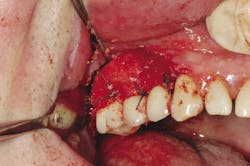

Clinical treatment of this disease is often determined by severity, but in general often includes flap surgery, bone grafts, membranes, growth factors, and/or soft-tissue grafts12 (Figs. 3 and 3a). The overall financial impact upon the patient for this type of treatment can be quite high considering the patient was already subject to initial start-up costs of treatment. (Table C). In addition, maintenance intervals after implant therapy should be equal to if not more stringent than those of natural teeth. The prevalence of peri-implantitis has been shown in some studies to range from 11% to as high as 47% of implant sites analyzed.13 A large disparity in percentages can be seen when comparing the prevalence of reoccurring periodontal disease after treatment vs. the percentage of implants that will demonstrate complications after prosthesis insertion. With that said, studies show that periodontal therapy has proven to be cost effective when compared to other types of tooth replacement therapy over a 15-year period evaluation.14